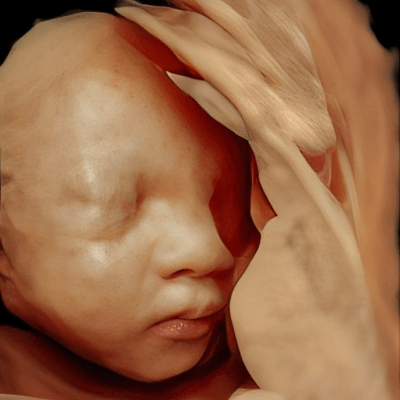

We present a case of Pfeiffer Syndrome with tympanic ring hypoplasia. Genetic amniocentesis revealed a pathogenic mutation in the FGFR2 gene.

Our ultrasound shows the typical features of Pfeiffer syndrome including premature fusion of the coronal sutures resulting in tower skull and brachycephaly, midface hypoplasia, a low nasal bridge, hypertelorism, and exophthalmos.